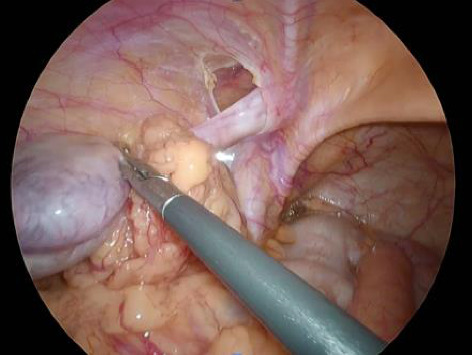

背景:隐睾是新生儿男性最常见的先天性异常之一,大多数在婴儿期诊断并在青春期前手术治疗。在某些情况下,隐睾是在成人腹股沟疝修补时偶然发现的,需要在手术时进行适当的处理。病例介绍:病例1:一名58岁男性因左侧嵌顿疝接受紧急腹腔镜手术。术中发现一例M2型腹股沟斜疝伴精索网膜绞窄。尽管试图用手把睾丸拉下来,但它没有下降到阴囊内,这导致了隐睾症的诊断。切除精索,放置3D网片覆盖疝缺损。病例2:一名33岁的努南综合征患者,表现为右腹股沟局部疼痛和肿胀。腹腔镜检查发现三层腹股沟斜疝,并发现腹腔内睾丸。发现睾丸和精管在腹腔内终止,确认隐睾的诊断。行睾丸切开术,将睾丸皮下固定于阴囊内,并用3D补片修复疝。结论:隐睾合并腹股沟疝行补片修补术的安全性已有文献报道。在术前因疼痛难以触诊的情况下,术中牵拉睾丸有助于区分隐睾症和收缩性睾丸。此外,睾丸切除术可作为一种临时措施,必要时可考虑分期切除。

Background: Cryptorchidism is one of the most common congenital anomalies in newborn males, with the majority diagnosed in infancy and treated surgically before puberty. In some cases, cryptorchid testes are discovered incidentally during inguinal hernia repair in adults, requiring appropriate management at the time of surgery. Case Presentation: Case 1: A 58-year-old male underwent emergency laparoscopic surgery for a left incarcerated hernia. Intraoperatively, an M2 indirect inguinal hernia with omental strangulation of the spermatic cord was identified. Despite attempts to pull the testis down manually, it did not descend into the scrotum, leading to the diagnosis of cryptorchidism. The spermatic cord was excised and a 3D mesh was placed to cover the hernia defect. Case 2: A 33-year-old man with Noonan syndrome presented with localized pain and swelling in the right groin. Laparoscopy revealed an indirect L3 inguinal hernia and incidentally an intra-abdominal testis was found. The testis and spermatic vessels were found to terminate intra-abdominally, confirming the diagnosis of cryptorchidism. An orchiopexy was performed to secure the testis subcutaneously in the scrotum and the hernia was repaired with a 3D mesh. Conclusion: The safety of mesh-based hernia repair in cases of cryptorchidism with concomitant inguinal hernia has been previously reported. In cases where preoperative palpation is difficult due to pain, intraoperative traction of the testis may help differentiate between cryptorchidism and retractile testis. In addition, orchiopexy may serve as a temporary measure, with consideration of staged orchiectomy if necessary.